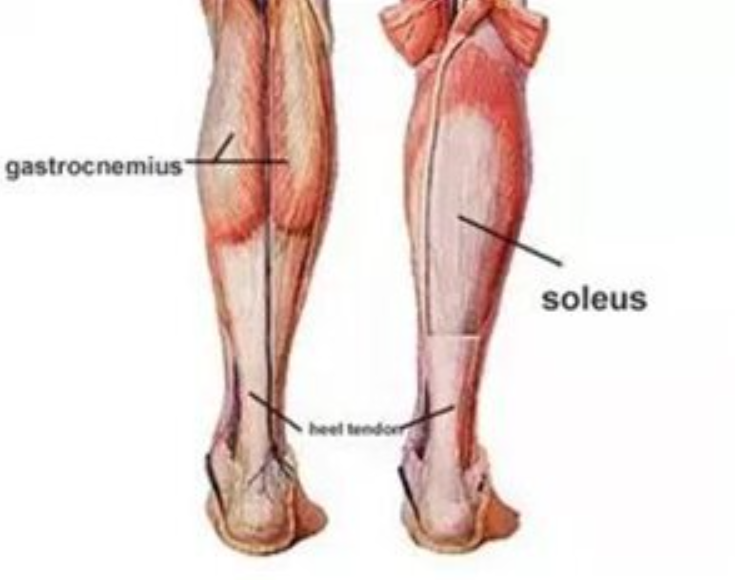

운동을 잘하는 발목과 못하는 발목의 차이는 ‘아킬레스건 길이’라는 게시글의 주장에 네티즌들은 공감하는 반응을 보였다.

이처럼 ‘운동 못하는 발목’에 해당하는 아킬레스건이 짧은 발목을 가진 사람들은 뒷꿈치를 붙이고 쪼그려 앉는 자세가 불가능하다고 알려지기도 했다.